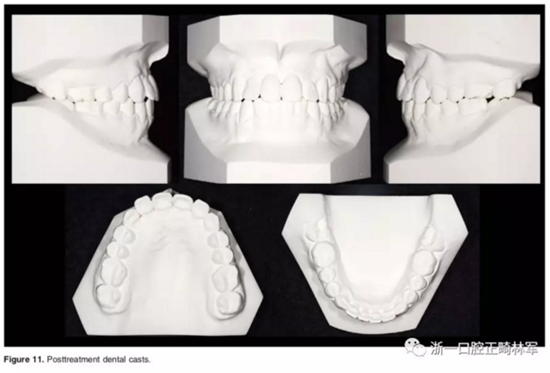

口外相:前牙易位、阻生均得以正確糾正,牙周組織健康。

口內(nèi)相及模型:I類尖牙、磨牙關(guān)系,覆合、覆蓋正常;中切牙與側(cè)切牙間有輕微的轉(zhuǎn)矩差;牙齦外形可;此外,在治療期間病人的口腔衛(wèi)生不夠良好,導(dǎo)致幾顆牙齒出現(xiàn)了齲病。

2年隨訪:咬合關(guān)系保持穩(wěn)定,無(wú)明顯復(fù)發(fā),下頜有一定晚期生長(zhǎng)趨勢(shì);前牙牙齦外形、牙冠高度無(wú)明顯變化;唇側(cè)牙槽骨高度、厚度均保持良好。